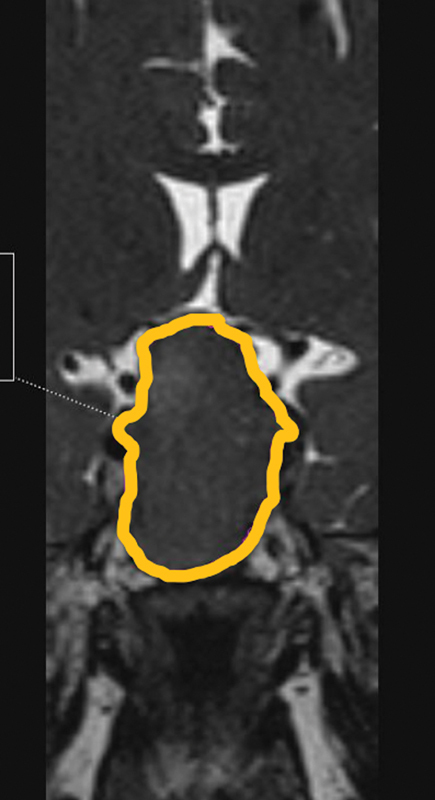

引言 内窥镜经蝶手术(ETS)是垂体手术的标准做法。在 ETS 中,蝶鞍暴露是决定残留疾病的主要因素。关于蝶鞍解剖变异对术中蝶鞍暴露影响的研究文献并不多。目的 本研究旨在确定蝶窦变异是否对蝶窦暴露和残余肿瘤体积有影响。方法 这是一项前瞻性研究,于 2020 年 6 月至 2022 年 6 月期间在印度南部的一家三级医疗中心进行,共有 21 名计划接受 ETS 的研究参与者。评估术前计算机断层扫描(CT)和磁共振成像(MRI)参数与术中蝶窦暴露面积和残余肿瘤体积的关系。结果 蝶窦尺寸,如蝶窦前宽(平均 = 1.89 ± 0.51 厘米)、最大宽度(平均 = 2.94 ± 1.09 厘米)、蝶窦前深(平均 = 1.14 ± 0.55 厘米)、蝶窦上深(平均 = 1.08 ± 0.24 cm)、髌下深度(平均 = 2.36 ± 0.92 cm)、髌前高度(平均 = 2.22 ± 0.47 cm)或 9 个颈内动脉(ICA)相关测量值与术中平均蝶鞍暴露面积(0.57 ± 0.28 cm 2)没有任何相关性。此外,蝶鞍暴露是否充分与残余肿瘤也没有关系。与无残留肿瘤的患者(5.9 [6.8-5.2] cm 3)相比,有残留肿瘤的患者术前肿瘤体积更高(20.2 [55.3-13.2] cm 3)。肿瘤的扩展与残留肿瘤体积有显著关系。结论 根据本研究,蝶窦的解剖变异不会影响蝶窦暴露的充分性。关于残余肿瘤体积以及术前肿瘤体积和扩展情况,还需要进一步研究。

Introduction  Endoscopic transsphenoidal surgery (ETS) is the standard practice in pituitary surgeries. The sellar exposure becomes the main factor which determines the residual disease in ETS. Not many studies can be found in the literature on the influence of anatomical variations of the sphenoid on intraoperative sella exposure. Objective  The aim of the current study is to ascertain whether sphenoid sinus variations play a role in sellar exposure and residual tumor volume. Methods  This is a prospective study conducted in a south Indian tertiary care center between June 2020 to June 2022, with 21 study participants who were scheduled to have ETS. The relation of preoperative computed tomography (CT) and magnetic resonance imaging (MRI) parameters with the intraoperative area of sellar exposure and residual tumor volume was evaluated. Results  Sphenoid sinus dimensions, like presellar width (mean = 1.89 ± 0.51 cm), maximum width (mean = 2.94 ± 1.09 cm), presellar depth (mean = 1.14 ± 0.55 cm), suprasellar depth (mean = 1.08 ± 0.24 cm), infrasellar depth (mean = 2.36 ± 0.92 cm), presellar height (mean = 2.22 ± 0.47 cm), or the 9 internal carotid artery (ICA)-related measures, did not have any correlation with the mean intraoperative area of sellar exposure (0.57 ± 0.28 cm 2 ). Also, the adequacy of sellar exposure did not relate to the residual tumor. Preoperative tumor volume was found to be higher (20.2 [55.3-13.2] cm 3 ) in patients with residual tumor compared with those with no residual tumor (5.9 [6.8-5.2] cm 3 ). Tumor extension had a significant association with the residual tumor volume. Conclusion  According to the present study, anatomical variations of the sphenoid sinus do not influence the adequacy of sellar exposure. Further studies need to be undertaken concerning residual tumor volume as well as preoperative tumor volume and extension.